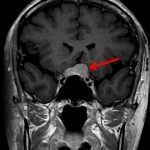

断層撮影

手術前1

手術前2